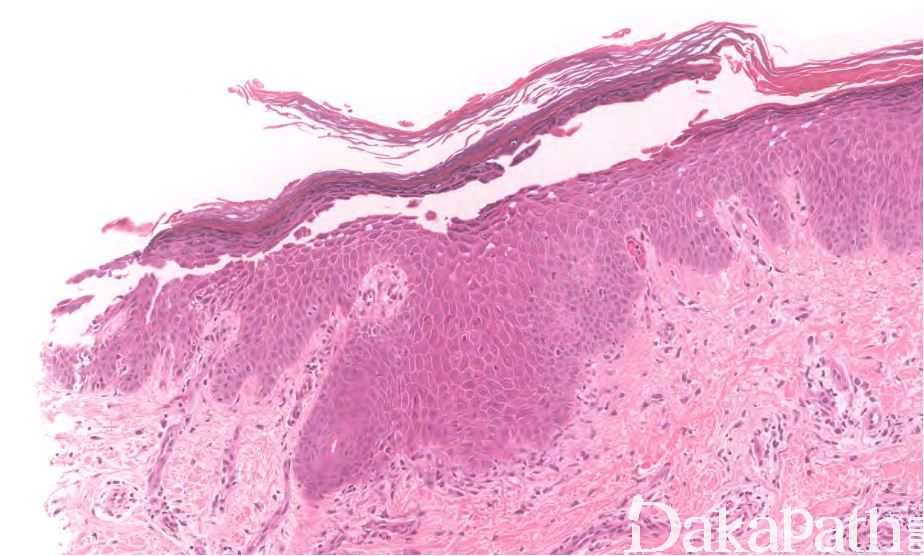

落叶性天疱疮

pemphigus foliaceus